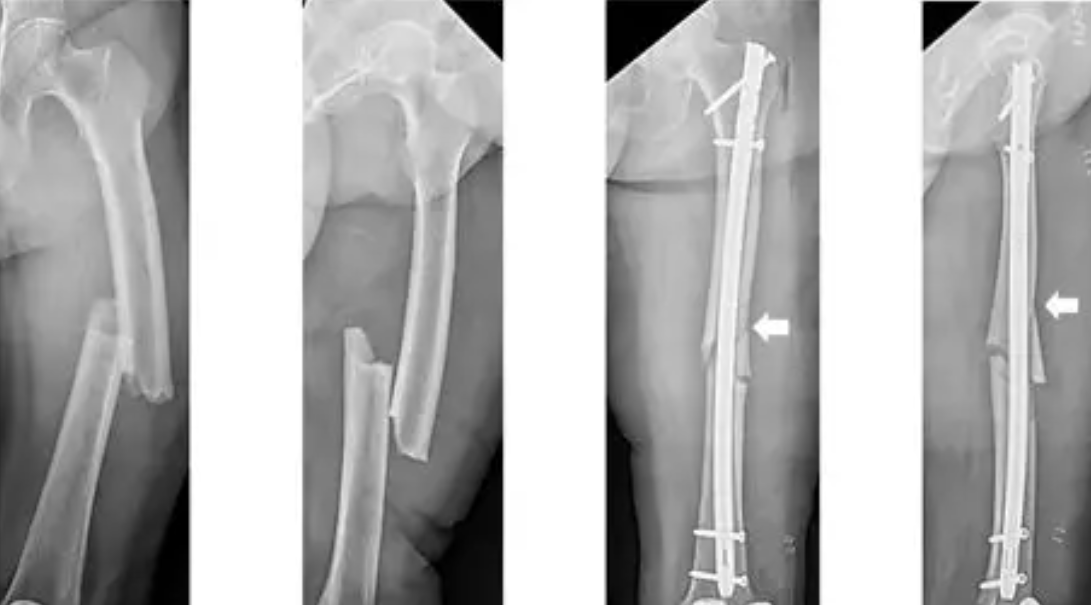

A surgery that stabilizes broken bones using screws, plates, or rods so they heal correctly.

The broken bone is aligned and fixed with metal implants that hold it until it heals naturally.